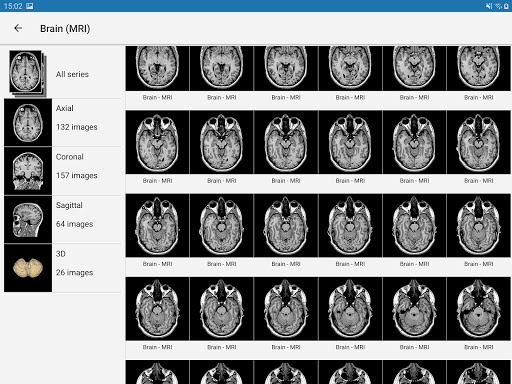

e-Anatomy memiliki lebih dari 26.000 gambar yang berisi serangkaian gambar dalam tampilan aksial, koronal, dan sagital serta radiografi, angiografi, gambar diseksi, bagan anatomi, dan ilustrasi. Semua gambar medis diberi label dengan cermat, lebih dari 967.000 label tersedia dalam 12 bahasa termasuk Terminologia Anatomica Latin.

- Gulir set gambar dengan menyeret jari Anda

- Perbesar dan perkecil